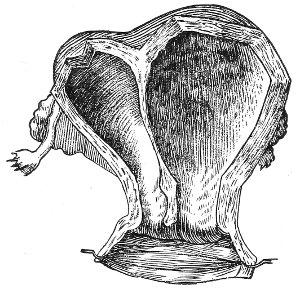

An accurate knowledge of the anatomy and mechanism of the female perineum is essential to an understanding of the nature and treatment of injuries to this structure. The anatomical structures lying between the anus behind and the symphysis pubis in front are those that most directly interest the gynecologist. Proceeding from 57 below upward, we find the following structures lying in superimposed planes: the skin, the superficial fascia, the deep layer of the superficial fascia, the transversus perinæi and the sphincter vaginæ muscles, the anterior layer of the triangular ligament, the posterior layer of the triangular ligament, the levator ani muscle (Fig. 19).

The vagina passes through these structures. They surround and support the ostium vaginæ as the fascia and muscles surround and support the opening of the rectum or the anus. The muscles and fasciæ are attached in the median line between the anus and the vagina, and therefore this part of the body, which is called the perineum, is supported or maintained in its 58 proper position by these various structures. The transversus perinæi arises from the ramus of the ischium and is inserted in the perineum. The bulbo-cavernosus, or sphincter vaginæ, arises in the perineum and is inserted in and about the clitoris. The inner fibers of the levator ani arise from the symphysis pubis and are inserted in the perineum and the lower part of the vagina (Fig. 20). When these muscles contract, their action, therefore, is to draw the perineum upward and forward. At the same time the anus is drawn upward and forward, and so also is the posterior margin of the ostium vaginæ and the lower portion of the posterior vaginal wall.

The vagina has no circular sphincter like the anus, but 59 the vaginal month is kept closed by the action of the transversus perinæi, sphincter vaginæ, and levator ani muscles, which draw the perineum forward, and thus keep the posterior vaginal wall in apposition with the anterior wall.

Fig. 21.—Muscular floor of the pelvis seen from above.

This sling of muscles and fascia, which surrounds and supports the opening of the vagina, may readily be felt in the nulliparous woman by introducing the finger in the vagina and pressing backward and outward toward the ischio-rectal fossa. We then feel plainly, immediately within the ostium vaginæ, a firm resisting band of tissue, apparently about half an inch broad, embracing the posterior portion of the lower vagina. This band is formed by the inner edges of the various muscles and planes of fascia that have been described.

Fig. 22.—Sagittal section showing relations of the several layers of fascia within the pelvic floor (Dickinson).

The vagina extends, as a transverse slit in the pelvic floor, upward and backward, approximately in the direction 60 of a line drawn from the ostium vaginæ to the fifth sacral vertebra. It is approximately parallel with the conjugate of the brim, so that when the woman is erect the long axis of the vagina is inclined at an angle of 60° to the horizon. The vagina is not a vertical open tube: it is a slit in the pelvic floor, in health always closed by the accurate apposition of the anterior and posterior walls (Fig. 21). The anterior vaginal wall is about 2½ inches long in a vertical mesial line. The posterior vaginal wall is about 3½ inches long. The vaginal walls are triangular in shape, being broader above than below. The shape of the normal vagina at the pelvic outlet is shown by Fig. 23. The section here shows the vaginal 61 slit of the shape of the letter H. The portions of the slit extending backward and somewhat outward are called the vaginal sulci or furrows. They are directions of diminished resistance in which tears are liable to occur.

The injuries to the perineum that may result from childbirth are classified according to the position or the direction and extent of the laceration. They are as follows: slight median tear; median tear involving the sphincter ani; tear in one or both of the vaginal sulci; subcutaneous laceration of the muscles and fascia.